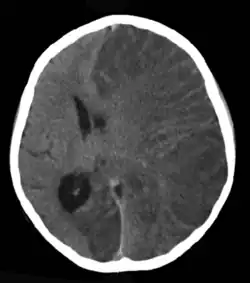

Brain CT scan without contrast enhancement of a patient, female, 8 years old, with Rasmussen's encephalitis.